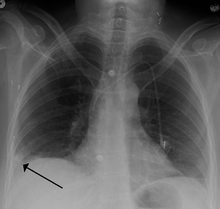

- Chest X-rays are often done on people with shortness of breath to help rule-out other causes, such as congestive heart failure and rib fracture. Chest X-rays in PE are rarely normal,[51] but usually lack signs that suggest the diagnosis of PE (for example, Westermark sign, Hampton's hump).